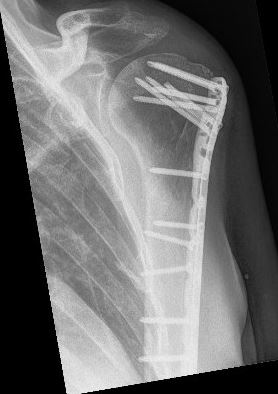

Indien u geopereerd moet worden, zal de traumachirurg de vorm van de kop willen herstellen en de kop of de fragmenten van de kop weer vast willen zetten aan de schacht. Hiervoor heeft uw traumachirurg verschillende opties, afhankelijk van het type breuk en de voorkeur van uw chirurg. Vaak gebruikt worden platen en schroeven om de verschillende breukdelen aan elkaar vast te zetten. Soms kan de chirurg ook besluiten de breuk met een pen en schroeven vast te zetten. Hiervoor is vaak een kleinere snede nodig dan bij een plaat met schroeven.

Meestal zult u na de operatie een mitella of draagband krijgen, zodat de arm rust kan krijgen. Hoe lang u na de operatie rust moet houden, is afhankelijk van het soort breuk en hoe stevig de chirurg de breukdelen weer aan elkaar heeft kunnen zetten. Meestal zal het zo zijn dat u tot 6 weken na de operatie uw arm niet mag belasten maar na 1 tot 2 weken wel voorzichtig mag gaan oefenen op geleide van de pijn om het schoudergewricht soepel te houden en verstijving zo veel mogelijk te voorkomen. Die oefeningen doet u door het bovenlichaam voorover te buigen, zodat de arm in de mitella vrij komt te hangen en u draaiende bewegingen kunt maken met de schouder. Bij deze oefening lijkt het alsof u in een grote pan roert, waarbij u in de loop van de tijd de pan steeds groter ‘maakt’. Ook is het verstandig tijdens de gehele periode zo nu en dan de arm uit de mitella te doen en de elleboog even te strekken.

U moet er rekening mee houden dat u al gauw meer dan 6-12 weken nodig heeft voordat u uw schouder weer enigszins goed kunt gebruiken. Vaak is belasten van de arm met kracht pas toegestaan als de breuk al enigszins is vastgegroeid, dit duurt in de regel minimaal zo’n 6 weken. Daarna kunt u pas de kracht en belasting gaan uitbreiden. Ook de beweeglijkheid kan dan pas verder worden uitgebreid. Vaak is nabehandeling met behulp van een fysiotherapeut hierbij nodig. Volledig normaal en pijnvrij gebruik van de schouder kan minstens 3-6 maanden of soms nog langer duren. Hou er rekening mee dat de kans bestaat dat de schouder nooit meer zo flexibel wordt als voor de val.